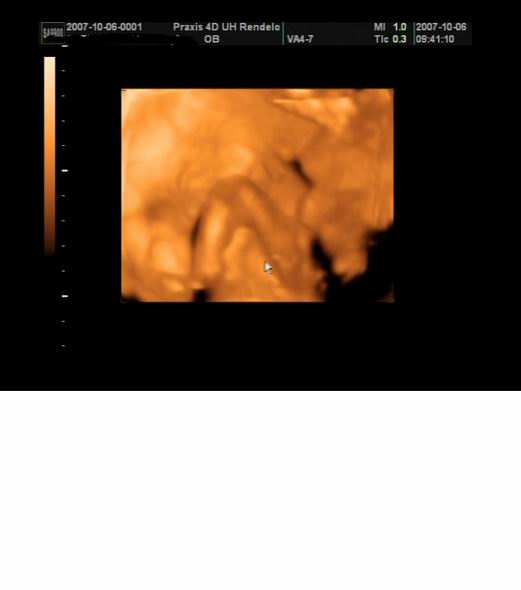

Most is Edi miatt írnék,pontosabban Neki szeretném mutatni a 18hetes Botondunkat :wink:

Kép